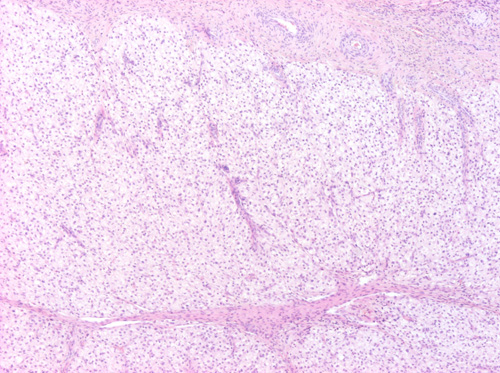

Histológicamente el ovario está constituido por una envoltura externa de epitelio simple cúbico sobre la túnica albugínea de tejido conjuntivo denso. El parénquima se diferencia en una zona cortical donde se desarrollan los folículos ováricos, y una zona medular muy vascularizada e innervada, que se continua con el hilio del órgano.

La zona cortical está constituida por los folículos en diversos grados de maduración, abundante estroma de tejido conjuntivo laxo. Se diferencian varios tipos de folículos según su fase de desarrollo. Los folículos primordiales están constituidos por el oocito (*) rodeado por una capa de células cúbicas (células foliculares), y se encuentran próximos a la superficie cortical. Los folículos primarios tienen un oocito de mayor tamaño rodeado por varias capas de células foliculares, que son las células de la granulosa (g). Entre el oocito y las células de la granulosa está la zona pelúcida (flecha). El estroma de alrededor se organiza formando las tecas (t). Entre las células de la granulosa y la teca está la membrana limitante externa (cabeza de flecha).

Señala la zona cortical del ovario